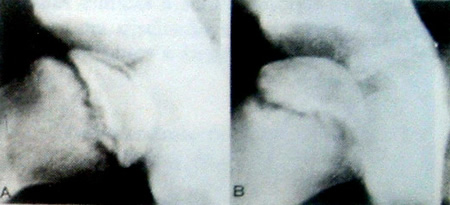

A doença de Panner manifesta-se por dor e tumefação discreta no cotovelo, assim como por restrição da movimentação articular. O aspecto radiológico é típico das osteocondroses em outras epífises de pressão (Fig.13-18). Como o cotovelo não é uma articulação de carga, e forças anormais e excessivas não são normalmente aplicadas ao capitellum, a deformidade é improvável e o prognóstico é bom. O tratamento consiste em prover a criança com uma tipóia durante o período de desconforto.

Figura 13-18. Osteocondrose do capítelo esquerdo (doença de Panner) em um menino de seis anos de idade. A. o cotovelo direito normal para comparação. B e C, note a combinação da rarefação provocada pela reabsorção óssea, e esclerose devido à deposição óssea dando a aparência de “fragmentação”. Note também o fenômeno de um “capítelo dentro de um capítelo”.